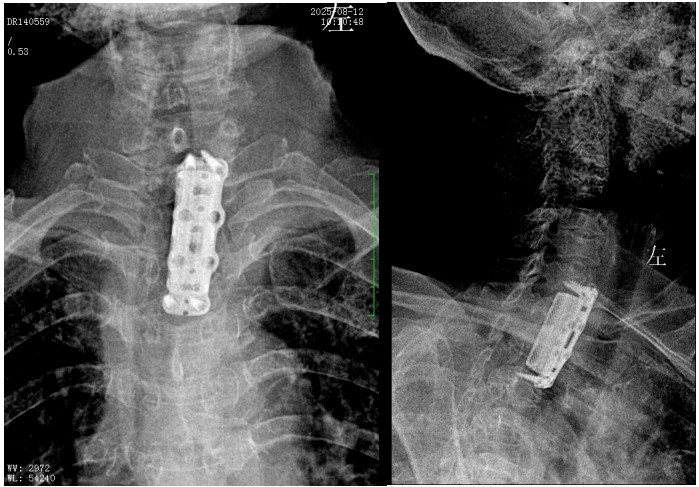

錢軍博士組織團隊進行了詳盡的術(shù)前討論,充分的術(shù)前準備后,于8月10日為患者實施了“前路病灶清除、人工椎體植入、植骨融合內(nèi)固定術(shù)”。順利完成了徹底清除病灶,椎管減壓解除脊髓壓迫,矯正后凸畸形,重建脊柱穩(wěn)定性的手術(shù)目標。

術(shù)后,脊柱外科醫(yī)護團隊為病人制定了快速康復(fù)方案,經(jīng)過精心治療與護理,李奶奶訴胸背部、雙上肢的疼痛癥狀較前明顯好轉(zhuǎn),晚上終于能睡個安穩(wěn)覺了。兩周后,李奶奶恢復(fù)良好,現(xiàn)已順利出院。